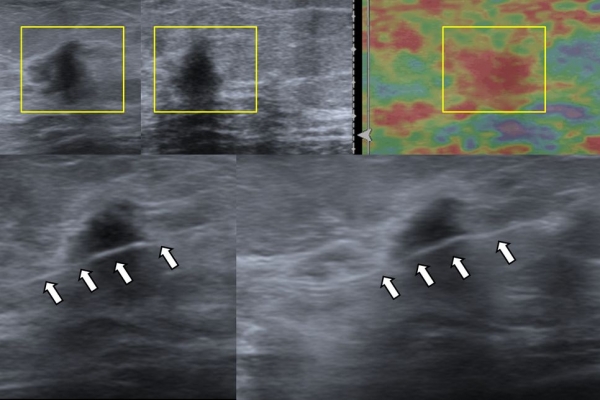

- Υπερηχογραφικά καθοδηγούμενη βιοψία μαστού - core biopsy

Εχει αντικαταστήσει την FNA στις συμπαγείς βλάβες του μαστού, γιατί η ποσότητα του ιστού που συλλέγεται είναι μεγαλύτερη και το αποτέλεσμα πιο αξιόπιστο.